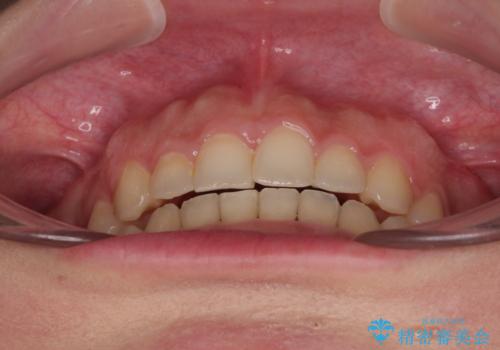

捻れて前に出ている前歯 ワイヤー装置での非抜歯矯正

- 捻れて前に出ている上顎前歯と全体的なデコボコを気にして来院された患者様です。

口元の突出感は強くなかったため非抜歯矯正での対応となりますが、捻転を改善する際に上顎前歯が前突する可能性があったため、上顎臼歯部にアンカースクリューを使用して、歯列が前方に転位しないようにすることとしました。